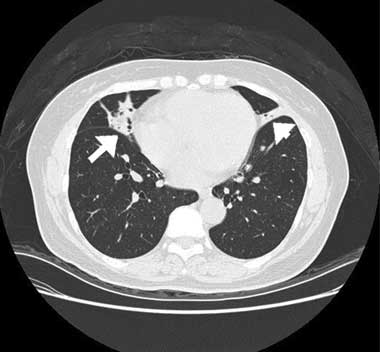

A computed tomography (CT) scan of the chest showed inhomogeneous opacities, as well as dilated airways crowded in the medial segment of the right middle lobe and inferior segment of the lingula, without mediastinal lymphadenopathy (Box, B). A fibrobronchoscopic examination to verify central bronchial patency showed no intraluminal obstruction in the affected bronchi. Cultures of the lavaged bronchial fluid were negative for tuberculosis and other microorganisms, and no malignant cells were found in aspirated specimens. A transbronchial biopsy from the atelectatic middle lobe revealed lymphocytic bronchiolitis with a moderate degree of mononuclear cell infiltration, predominantly by lymphocytes, in the terminal bronchiolar walls and adjacent interstitial areas, and no granuloma formation (Box, C).